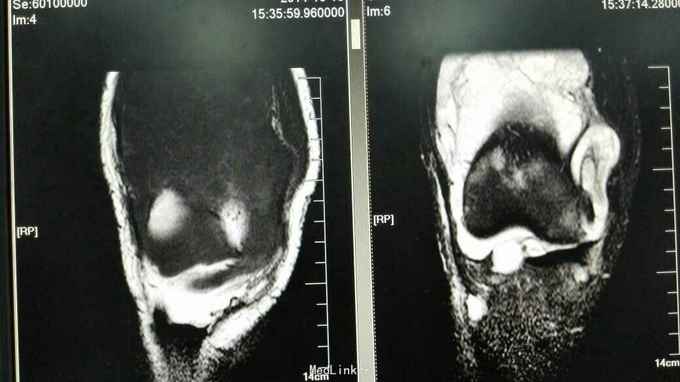

查体:右膝稍肿胀,皮温正常,右膝髌上囊处压痛(+),右膝屈曲稍受限(0~100度),余查体正常。 辅助检查:血常规、ESR、CRP正常 膝关节正侧位片:右膝关节退行性变,髌上囊肿胀 膝关节MRI提示:右膝髌上囊软组织占位,侵犯至股四头肌,考虑滑膜肉瘤可能性大 关节镜取活检提示滑膜肉瘤 全身PET-CT未见其它部位转移,肺无转移

诊断:右膝关节滑膜肉瘤 治疗:右大腿中上段截肢术